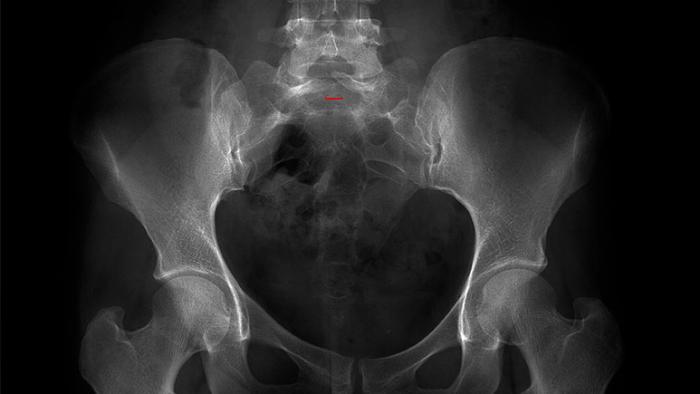

És un tipus de càncer situat als ossos o als teixits tous. El sarcoma d’Ewing és el segon càncer d’os més comú en infants, i normalment es presenta entre els deu i els vint anys. També és més comú en homes que en dones. El sarcoma d’Ewing i els tumors neuroectodèrmics primitius (PNET) són un tipus de càncer que inclouen diversos tipus de tumors malignes que comparteixen una anormalitat cromosòmica comuna. Els tumors d’Ewing estan formats per cèl·lules petites no diferenciades i acostumen a trobar-se amb més freqüència en un dels ossos llargs de la cama o del braç, en els ossos plans de les costelles o la pelvis, o a la columna. També pot ser que es presentin en qualsevol altre os del cos o en teixits tous.

El tumor d’Ewing situat en el teixit tou, s’anomena sarcoma d’Ewing extraesquelètic. I se sol donar a la cuixa, a la pelvis, a àrees de la columna, a la paret del tòrax o al peu.